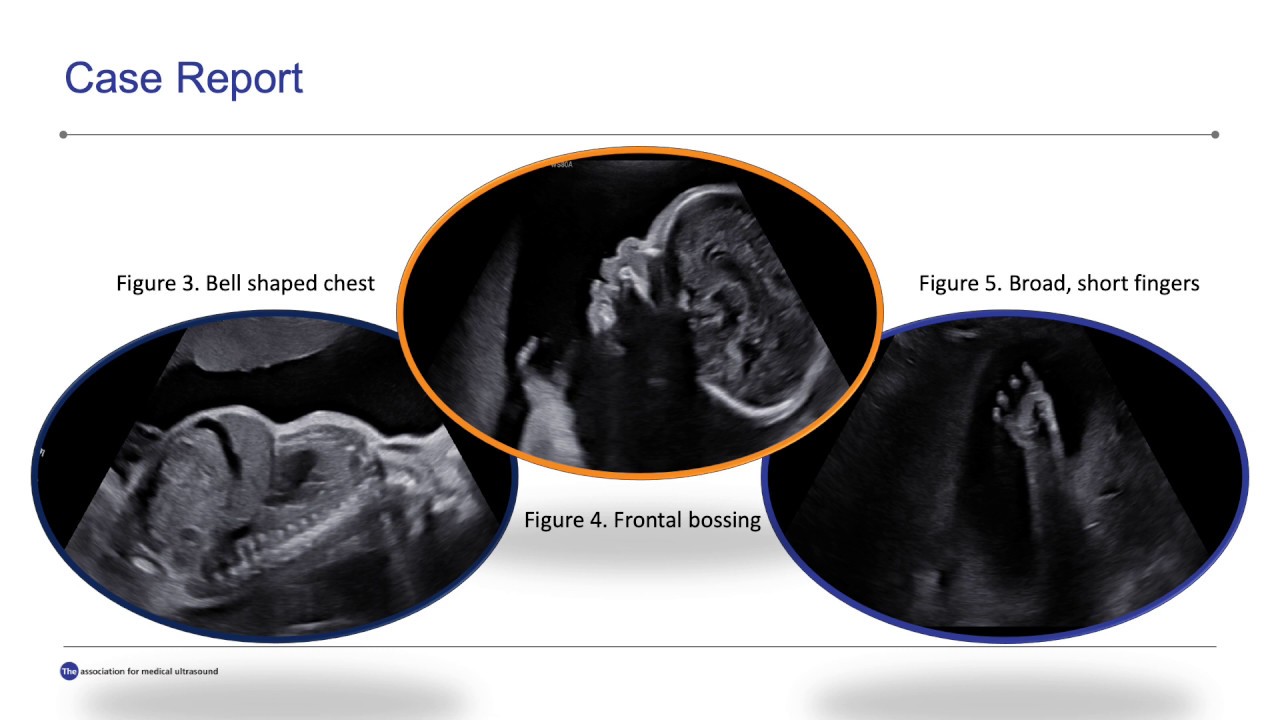

Thanatophoric Skeletal Dysplasia A Case Report and Review of Skeletal Radiology Case Report assessing the current role of ap and bernageau view radiographs in measurement of glenoid bone loss in. (1) scientific article, (2) review article, (3) case report, (4) perspective, (5). Adopts an interdisciplinary approach to cover a. metabolic bone diseases are a diverse group of diseases that result in abnormalities of bone mass, structure. in 2019, skeletal radiology. Skeletal Radiology Case Report.